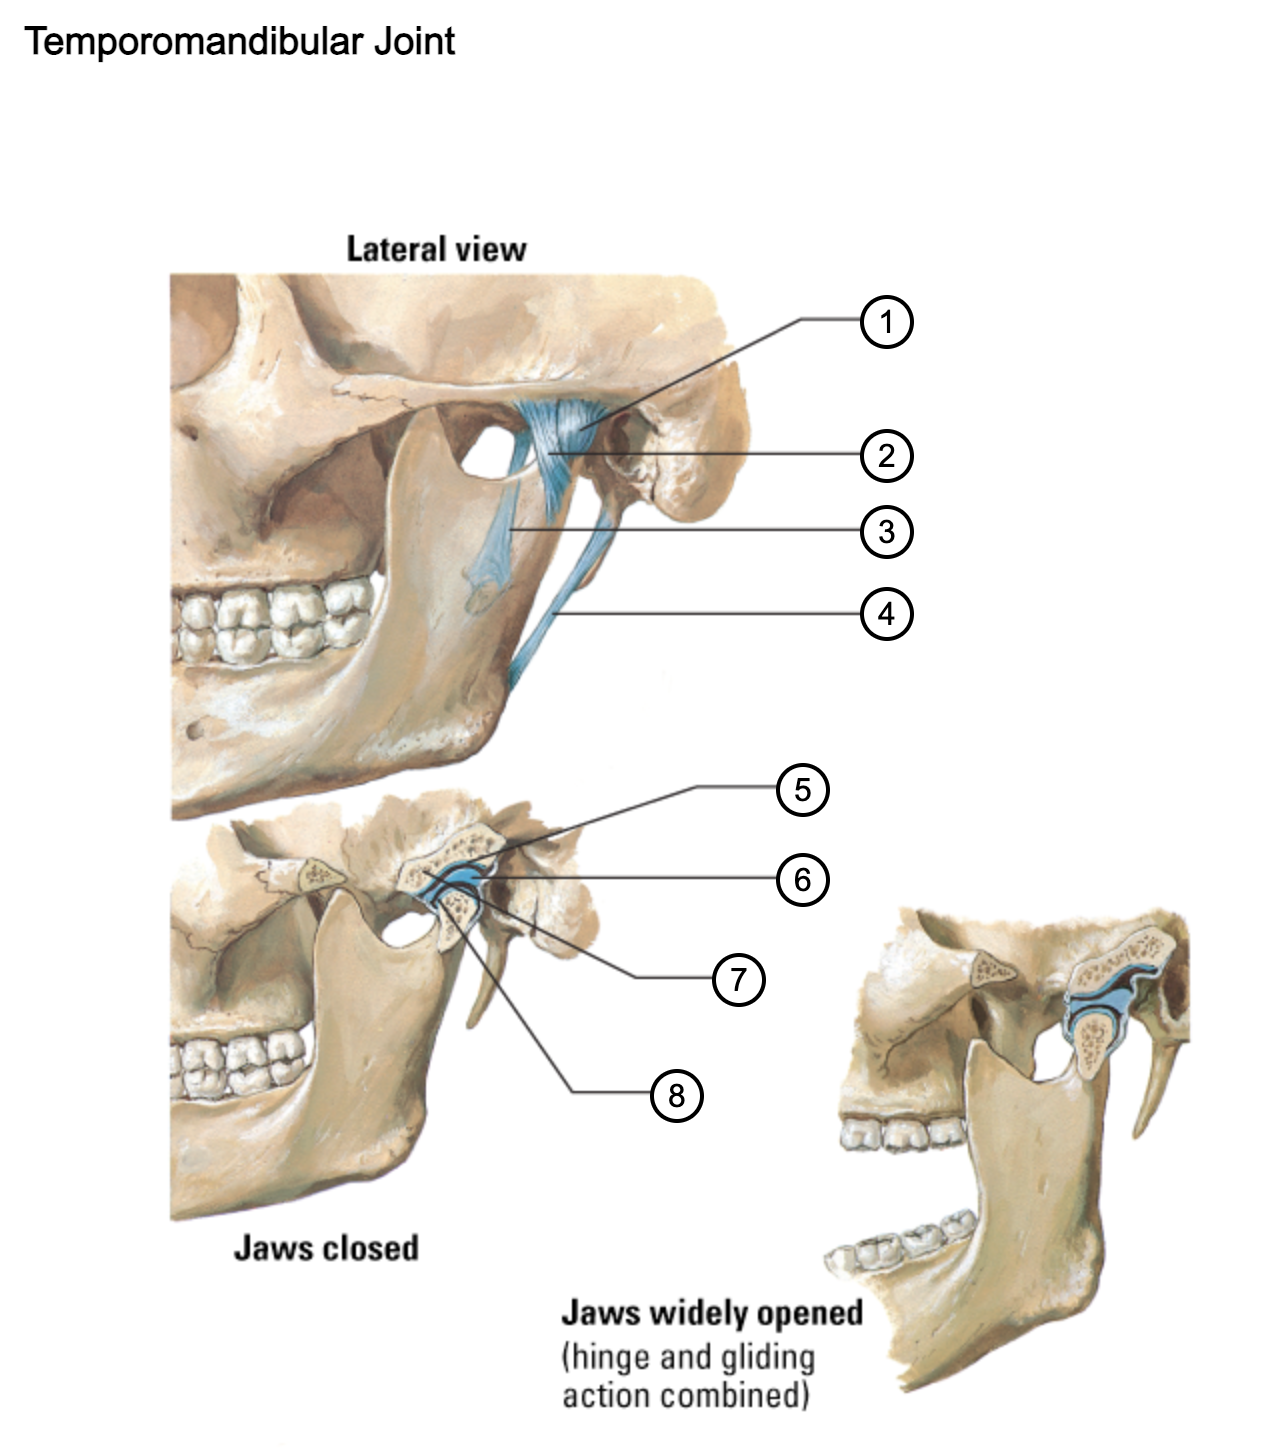

1

capsule of temporomandibular joint

2

lateral temporomandibular ligament

3

sphenomandibular ligament

4

stylomandibular ligament

5

mandibular fossa

6

articular disc

7

articular tubercle

8

capsule of temporomandibular joint